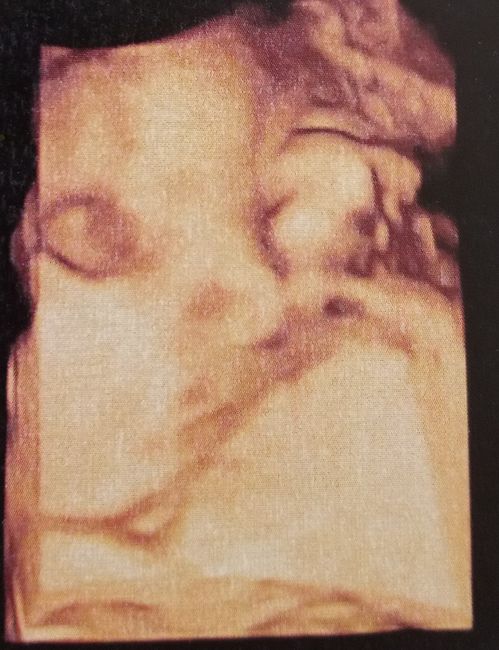

Future mamme maggio 2020

Da Simona , Il 26 Marzo 2020 alle 13:41

Apro ufficialmente il topic delle mamme di maggio 2020.Con molta felicità e anche paura, ma sono contenta che il mio arcobaleno sia tornato.DDP 12.5.2020 ...